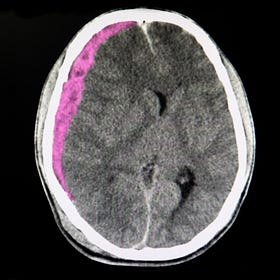

Middle meningeal artery embolization for subdural hematoma

Adjunctive embolization in subacute or chronic subdural hematoma (EMBOLISE trial)